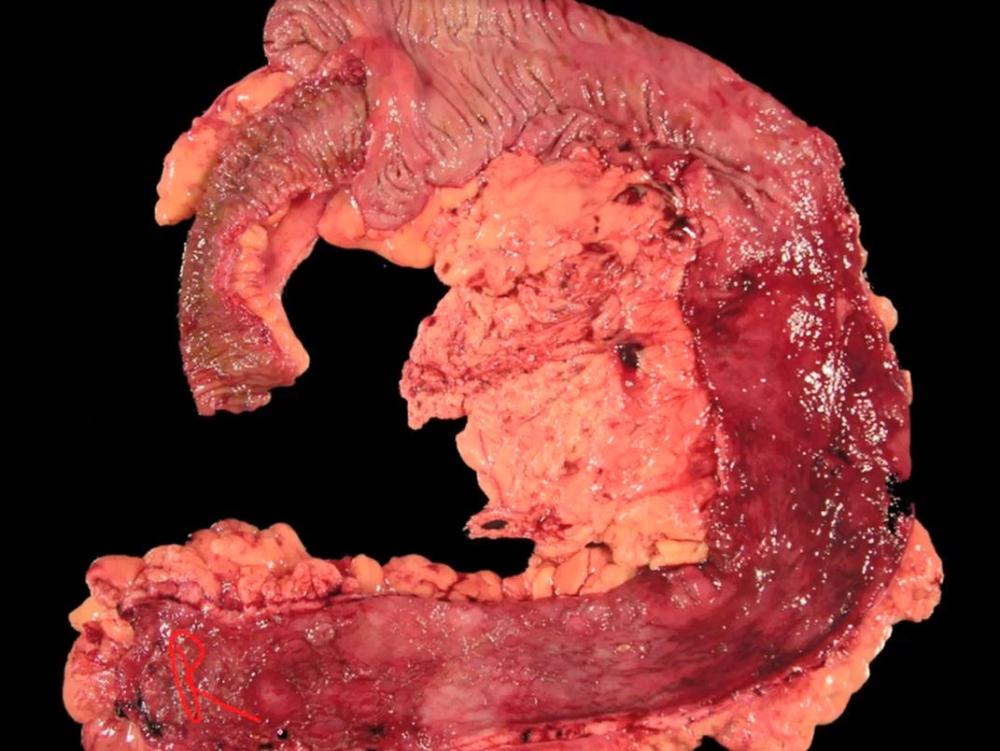

card image

meckel diverticulum